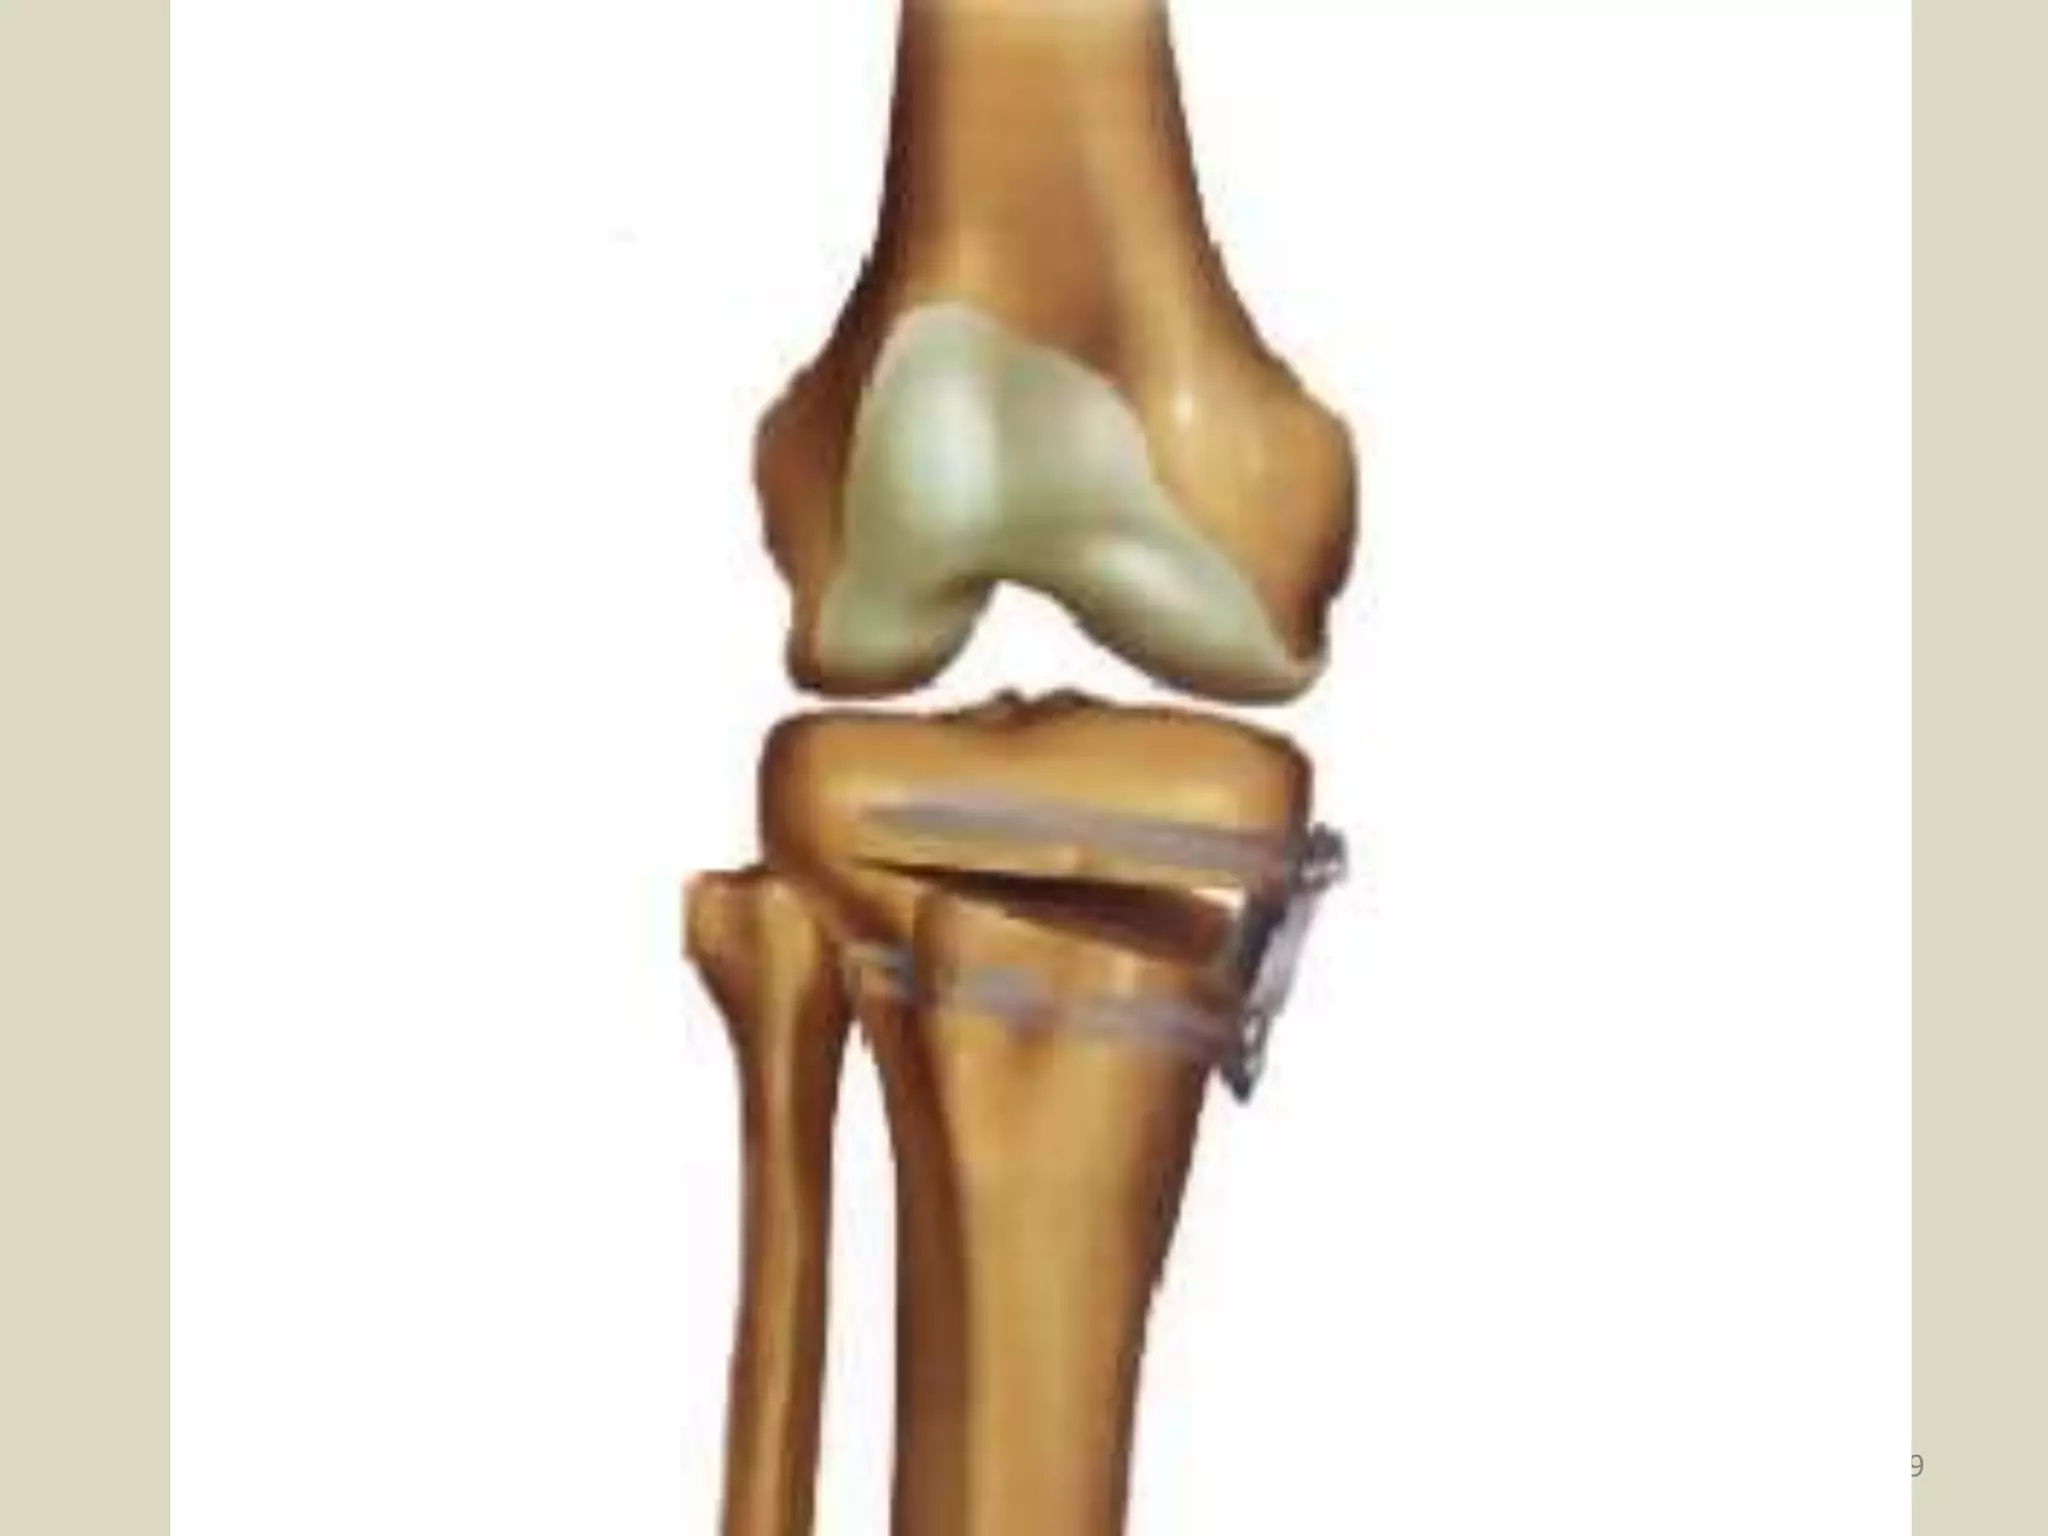

HIGH TIBIAL

CORRECTIVE OSTEOTOMY

29